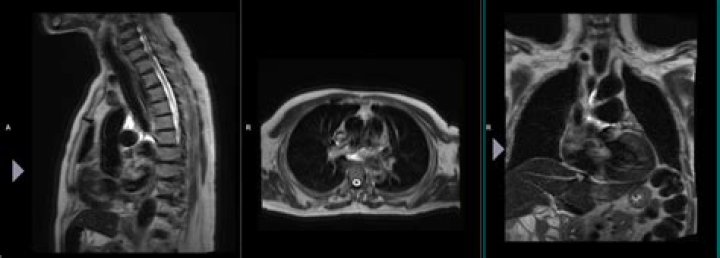

Localizer scans. A set of three-plane, low-resolution, large field-of view localizers are first obtained, equivalent to “scout views” in CT. These localizer images will be used for plotting slices in step 6. 5.

Localizer images, also called scout images, are used in MR and CT studies to identify the relative anatomical position of a collection of cross-sectional images. A localizer can be acquired as a separate image, as is often done for CTs, or it can be dynamically generated, as is done for MRs.

This coordinate system consists of three planes to describe the standard anatomical position of a human. The basic orientation terms for a MRI of the body taken: From the side would be a sagittal plane; from the front, would be a coronal plane; and from the top down, would be a transverse plane.

Localizer – a 3-plane localizer or ‘scout’ scan meant to find the subject’s head. It is also be used for prescription for the subsequent scans. Doing some sort of localizer is necessary, and the ‘3planeloc SSFSE’ (single shot fast spin echo) is the standard work-horse used by most CNI users.